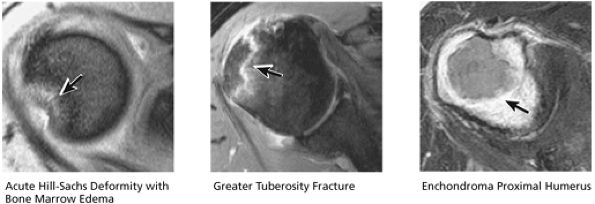

FIGURE 8.30 ● Axial images through the AC joint should be obtained on all shoulder MR examinations. (A) Axial T1- or PD-weighted images at this location are used to identify fractures of the distal clavicle and to demonstrate an os acromiale. (B) Axial FS PD-weighted images show cartilage covering the distal aspect of the clavicle and the medial aspect of the acromion at the AC joint. Cartilage defects and thinning, as well as subchondral bone marrow edema and cystic change, are evaluated on axial images through the AC joint. These degenerative changes can mimic the symptoms of a rotator cuff tear. (C) Axial T1- or PD-weighted images demonstrate the Hill-Sachs lesion of the humeral head, usually visualized as focal flattening or concave deformities in the posterolateral humeral head. The Hill-Sachs lesions is identified on the first or second superior axial image through the humeral head. Subcortical cystic change is more commonly visualized in the posterolateral humeral head and is usually an incidental finding in asymptomatic patients. (D) Axial FS PD-weighted images depict the biceps tendon coursing across the anteromedial aspect of the humeral head, within the rotator interval. This image location serves as a starting point for following the remainder of the biceps tendon into the bicipital groove on successive axial images moving from cranial to caudal. Tears of the supraspinatus and infraspinatus tendons are also identified at this image location on axial images. (E) Axial T1- or PD-weighted images allow evaluation of subcoracoid impingement. (F) In this location, thickening and increased signal in the superior glenohumeral ligament and coracohumeral ligament on an axial FS PD-weighted image may indicate adhesive capsulitis, particularly when accompanied by thickening and increased signal within the inferior glenohumeral ligament. (G) Axial T1- or PD-weighted images are used to identify subcortical cystic change in the greater and lesser tuberosity. This finding is commonly an indirect indication of abnormality or tearing in the overlying distal supraspinatus and subscapularis tendons, respectively. (H) Axial FS PD-weighted images through the proximal bicipital groove are used to identify “hidden lesions,” which are diagnosed when the biceps tendon is medially subluxing out of the bicipital groove, usually into a distal subscapularis tear or anterior to the lesser tuberosity. A degenerated biceps tendon may appear flattened and elongated as it rounds the lesser tuberosity into the proximal bicipital groove. Commonly, only the medial “tail” of the flattened degenerated biceps tendon subluxes out of the groove; the remainder of the flattened biceps tendon stays within the groove. (I) Axial T1- or PD-weighted images display the osseous glenoid subchondral surface, which should appear flat. Osseous glenoid remodeling, hypertrophy, deformity, subchondral cystic change, and edema are commonly identified as indirect evidence of overlying chronic cartilage degeneration or prior trauma. Posterior glenoid spurring may completely replace a degenerated or markedly attenuated posterior labrum. (J) Axial FS PD-weighted images are optimal for displaying the glenoid and humeral head cartilage. Chondral fissures, thinning, and defects are visualized when viewing successive cranial-to-caudal images through the glenohumeral joint. The anterior and posterior labrum are also optimally visualized and are normally firmly adherent to the glenoid and glenoid articular cartilage. (K) Axial T1- or PD-weighted images are used to identify bony Bankart lesions. These lesions are seen on inferior axial images through the glenohumeral ligament as oblique fracture lines extending through the anterior inferior glenoid. (L) Axial FS PD-weighted images show the prominent anterior band of the IGHL, which is occasionally mistaken for a tear of the anterior inferior labrum when fluid is interposed between the anterior band and the normal labrum.

The proximal humerus consists of the head, anatomic neck, and the greater and lesser tuberosities. The intertubercular or bicipital groove is located between the greater and lesser tuberosities along the anterior surface of the humerus. A decrease in the height of the medial wall of the lesser tuberosity and the presence of a supratubercular ridge of bone projecting from the superolateral aspect of the lesser tuberosity may predispose to instability of the biceps tendon within the groove, but dislocation or subluxation of the biceps tendon is extremely rare in the absence of a massive rotator cuff tear.